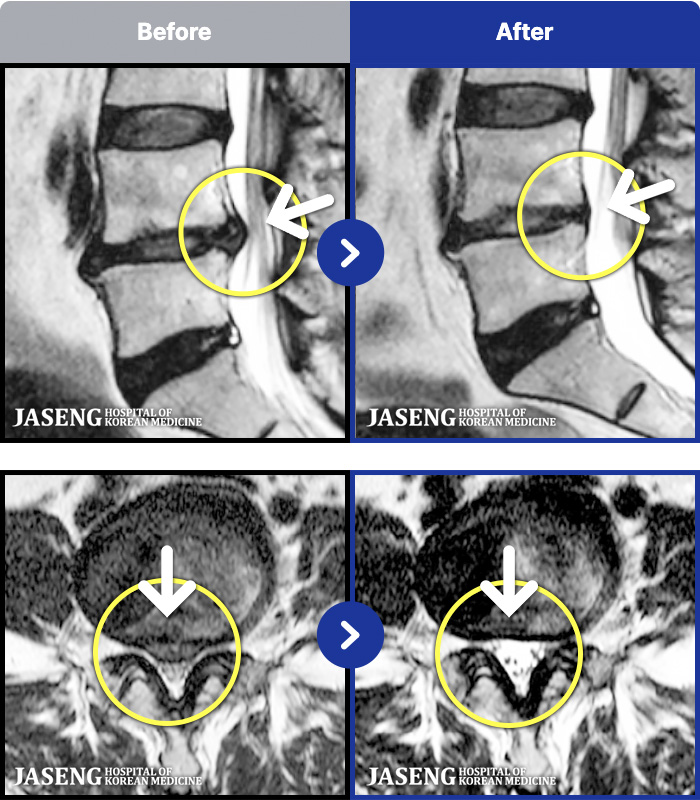

191 MRI ũ ʸ Ȯϼ.

ȯںп Ǹ ǿ ԿǾ, ο ġ ۿ Ƿ ġḦ Ͻñ ٶϴ.